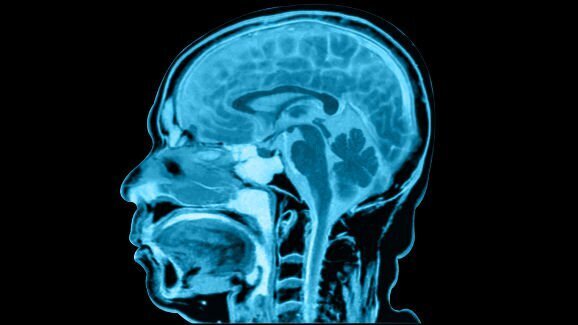

Podle Dr. Burgesse mohla být nejpravděpodobnějším vysvětlením stavu tohoto muže jistá forma anterográdní amnézie. V tomto případě poškození hippokampů, částí mozku odpovědných za upevňování informací z krátkodobé paměti v paměti dlouhodobé, takže se vzpomínky nemohou vytvářet a správně ukládat. Přesto skenování mozku tohoto muže neukázalo žádné abnormality. Dalším možným vysvětlením tak mohla být psychogenní nemoc. Dr. Burgess provedl podrobnou psychiatrickou analýzu s cílem zjistit, zda muž neutrpěl nějaké trauma. Dr. Burgess však zjistil, že byl pacient emočně zdráv a jeho manželka potvrdila, že před návštěvou zubního lékaře v roce 2005 nebyly v jeho životě žádné traumatické události.

Dr. Burgess pokračoval ve zkoumání vzácného případu amnézie svého pacienta, a měl podezření, že by důležitou roli mohly hrát synapse v mozku. Pokaždé, když se vytváří vzpomínka a přenáší se do dlouhodobé paměti, dochází k přestavbě synapsí, která zahrnuje produkci nových proteinů. Tato syntéza proteinů může být v případě tohoto pacienta blokována, což mu brání ve vytváření nových dlouhodobých vzpomínek. Za účelem dalšího zkoumání této hypotézy prošetřoval dr. Burgess z literatury pět podobných případů záhadné ztráty paměti bez poškození mozku. Tyto případy mohly poskytnout odpověď na otázku, proč se zdá, že ztrátu paměti muže spustilo ošetření kořenových kanálků. Všechny případy nějakým způsobem souvisely s obdobím psychického stresu během lékařského ošetření. „Mohlo se jednat o genetické predispozice, které potřebují ke spuštění procesu katalytickou událost,“ řekl dr. Burgess BBC.